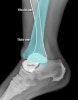

X-ray : 발목 관절 탈구(Ankle dislocation)

AP, lateral, Mortise view를 보면 대부분의 골절과 탈구가 진단됩니다.